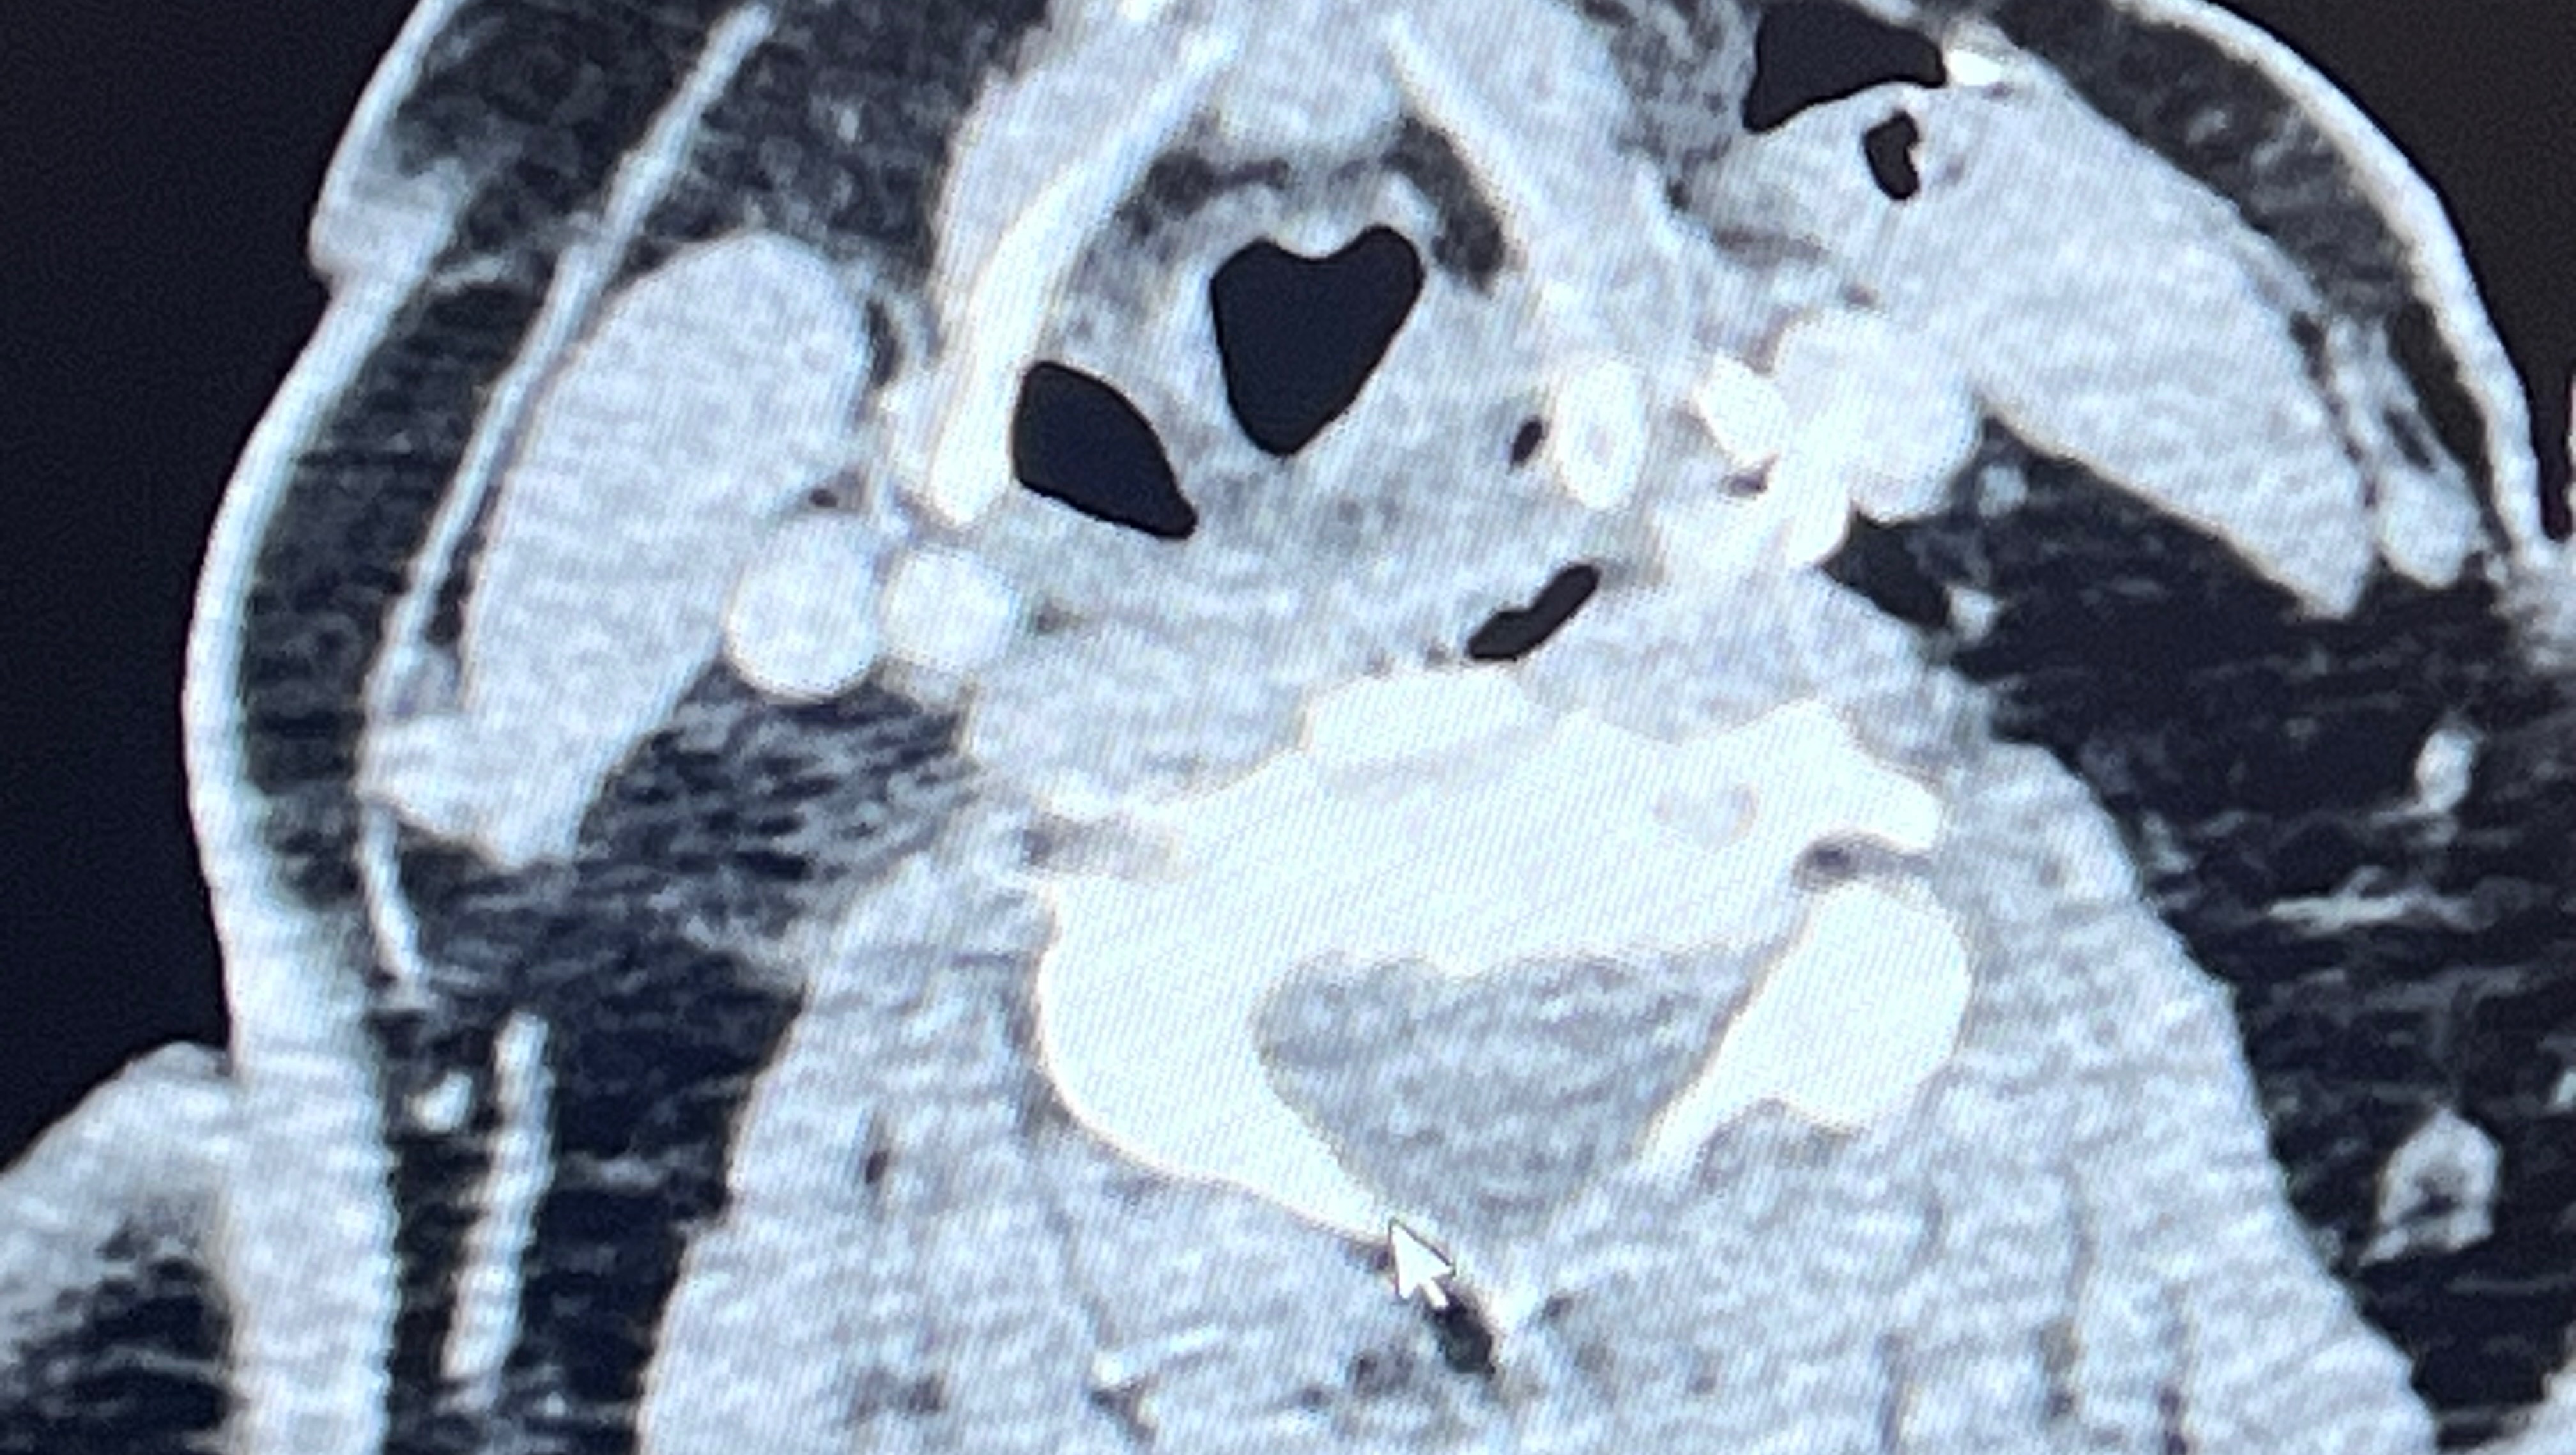

Over the last 10 + years Rori has developed Myoclonic and Tonic clonic seizures. They have rapidly increased and affect all of her daily life. Her last 43 hour brain scan (EEG) showed over 150 seizures. Over the last 2 years the seizures and the medication side effects got so bad she had to stop her business. Some days she has problems forming basic sentences, cooking, and even basic chores. Nathan is trying as hard as he can to continue to support their family while driving Rori to all the doctors appointments from eastern Washington to UW medical in western Washington for doctors, all shopping pretty much everything that needs to be done. This coming week, Rori will be going in for a surgery that is like a pace maker for her brain that will send a pulse through her brain to help send shock waves to hopefully help her have less seizures. Between this and the 4 medications she takes, she hopes to regain somewhat of a normal life for a bit. After surgery, every 1.5 to 2 weeks Nathan will need to take the day off, take Rori to the doctor to have the device calibrated for the next 6 plus months. Between this and missing work, and the 200 miles round trip it’s going to add up. The surgery bill, the hospital stay, the hotel stay for Nathan, and much more is all beginning to add up and weighing on Nathan’s shoulders as he tries to care for his wife.